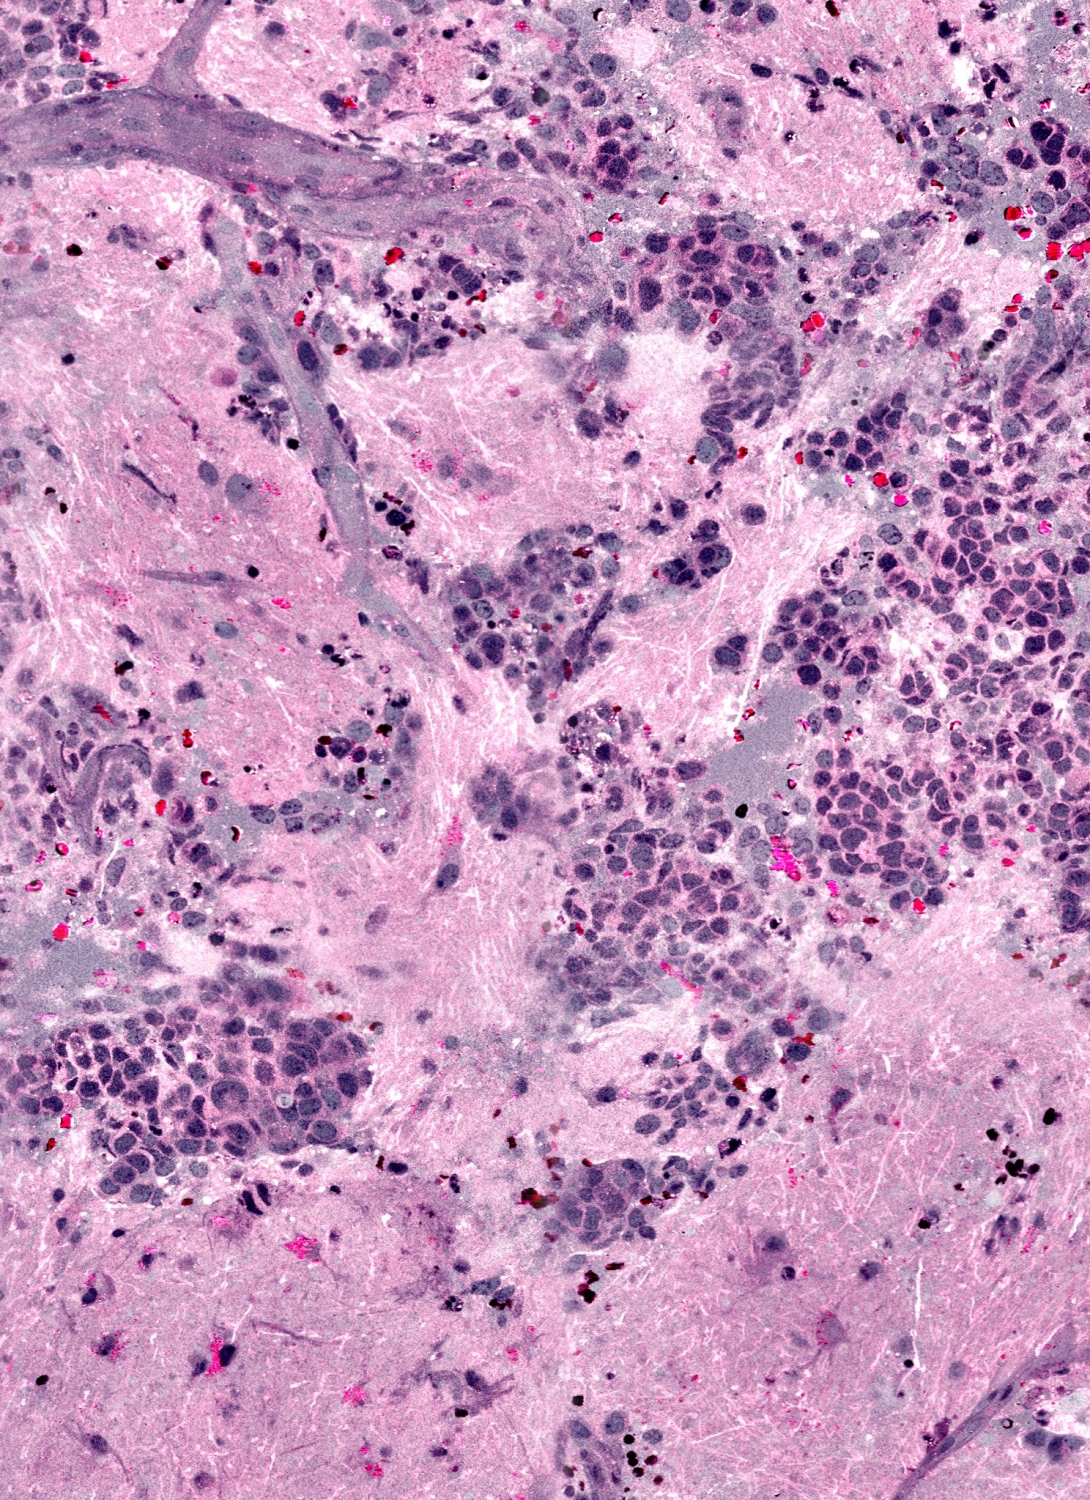

SRH uses virtual coloring to highlight the cellular and architectural features of brain tumors, with a result resembling traditional staining. The pathologist is then able to differentiate the tumor tissue from normal brain as usual.

"It's very similar to what we currently do in our intraoperative diagnosis, with the exception that the tissue is fresh, has not been processed or stained," says senior author Sandra Camelo-Piragua, M.D., assistant professor of pathology at U-M.